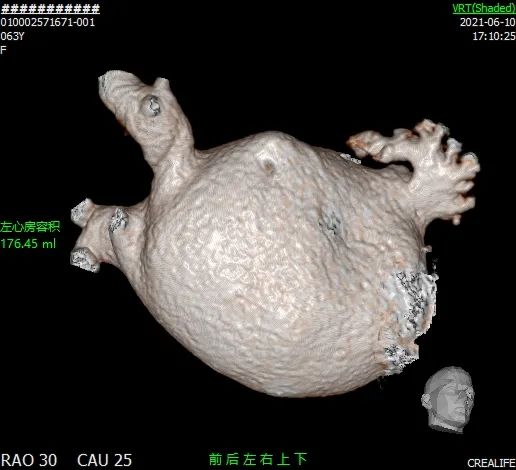

术后2个月CT三维重建,直观查看封堵器植入形态,且从二维图像来看,未见残余分流。

术后

封堵后透明三维

术后2个月未完全内皮化,未见DRT。

CT随访后提示左心耳封堵完全,遂停用达比加群,予以双联抗血小板药物进行治疗。